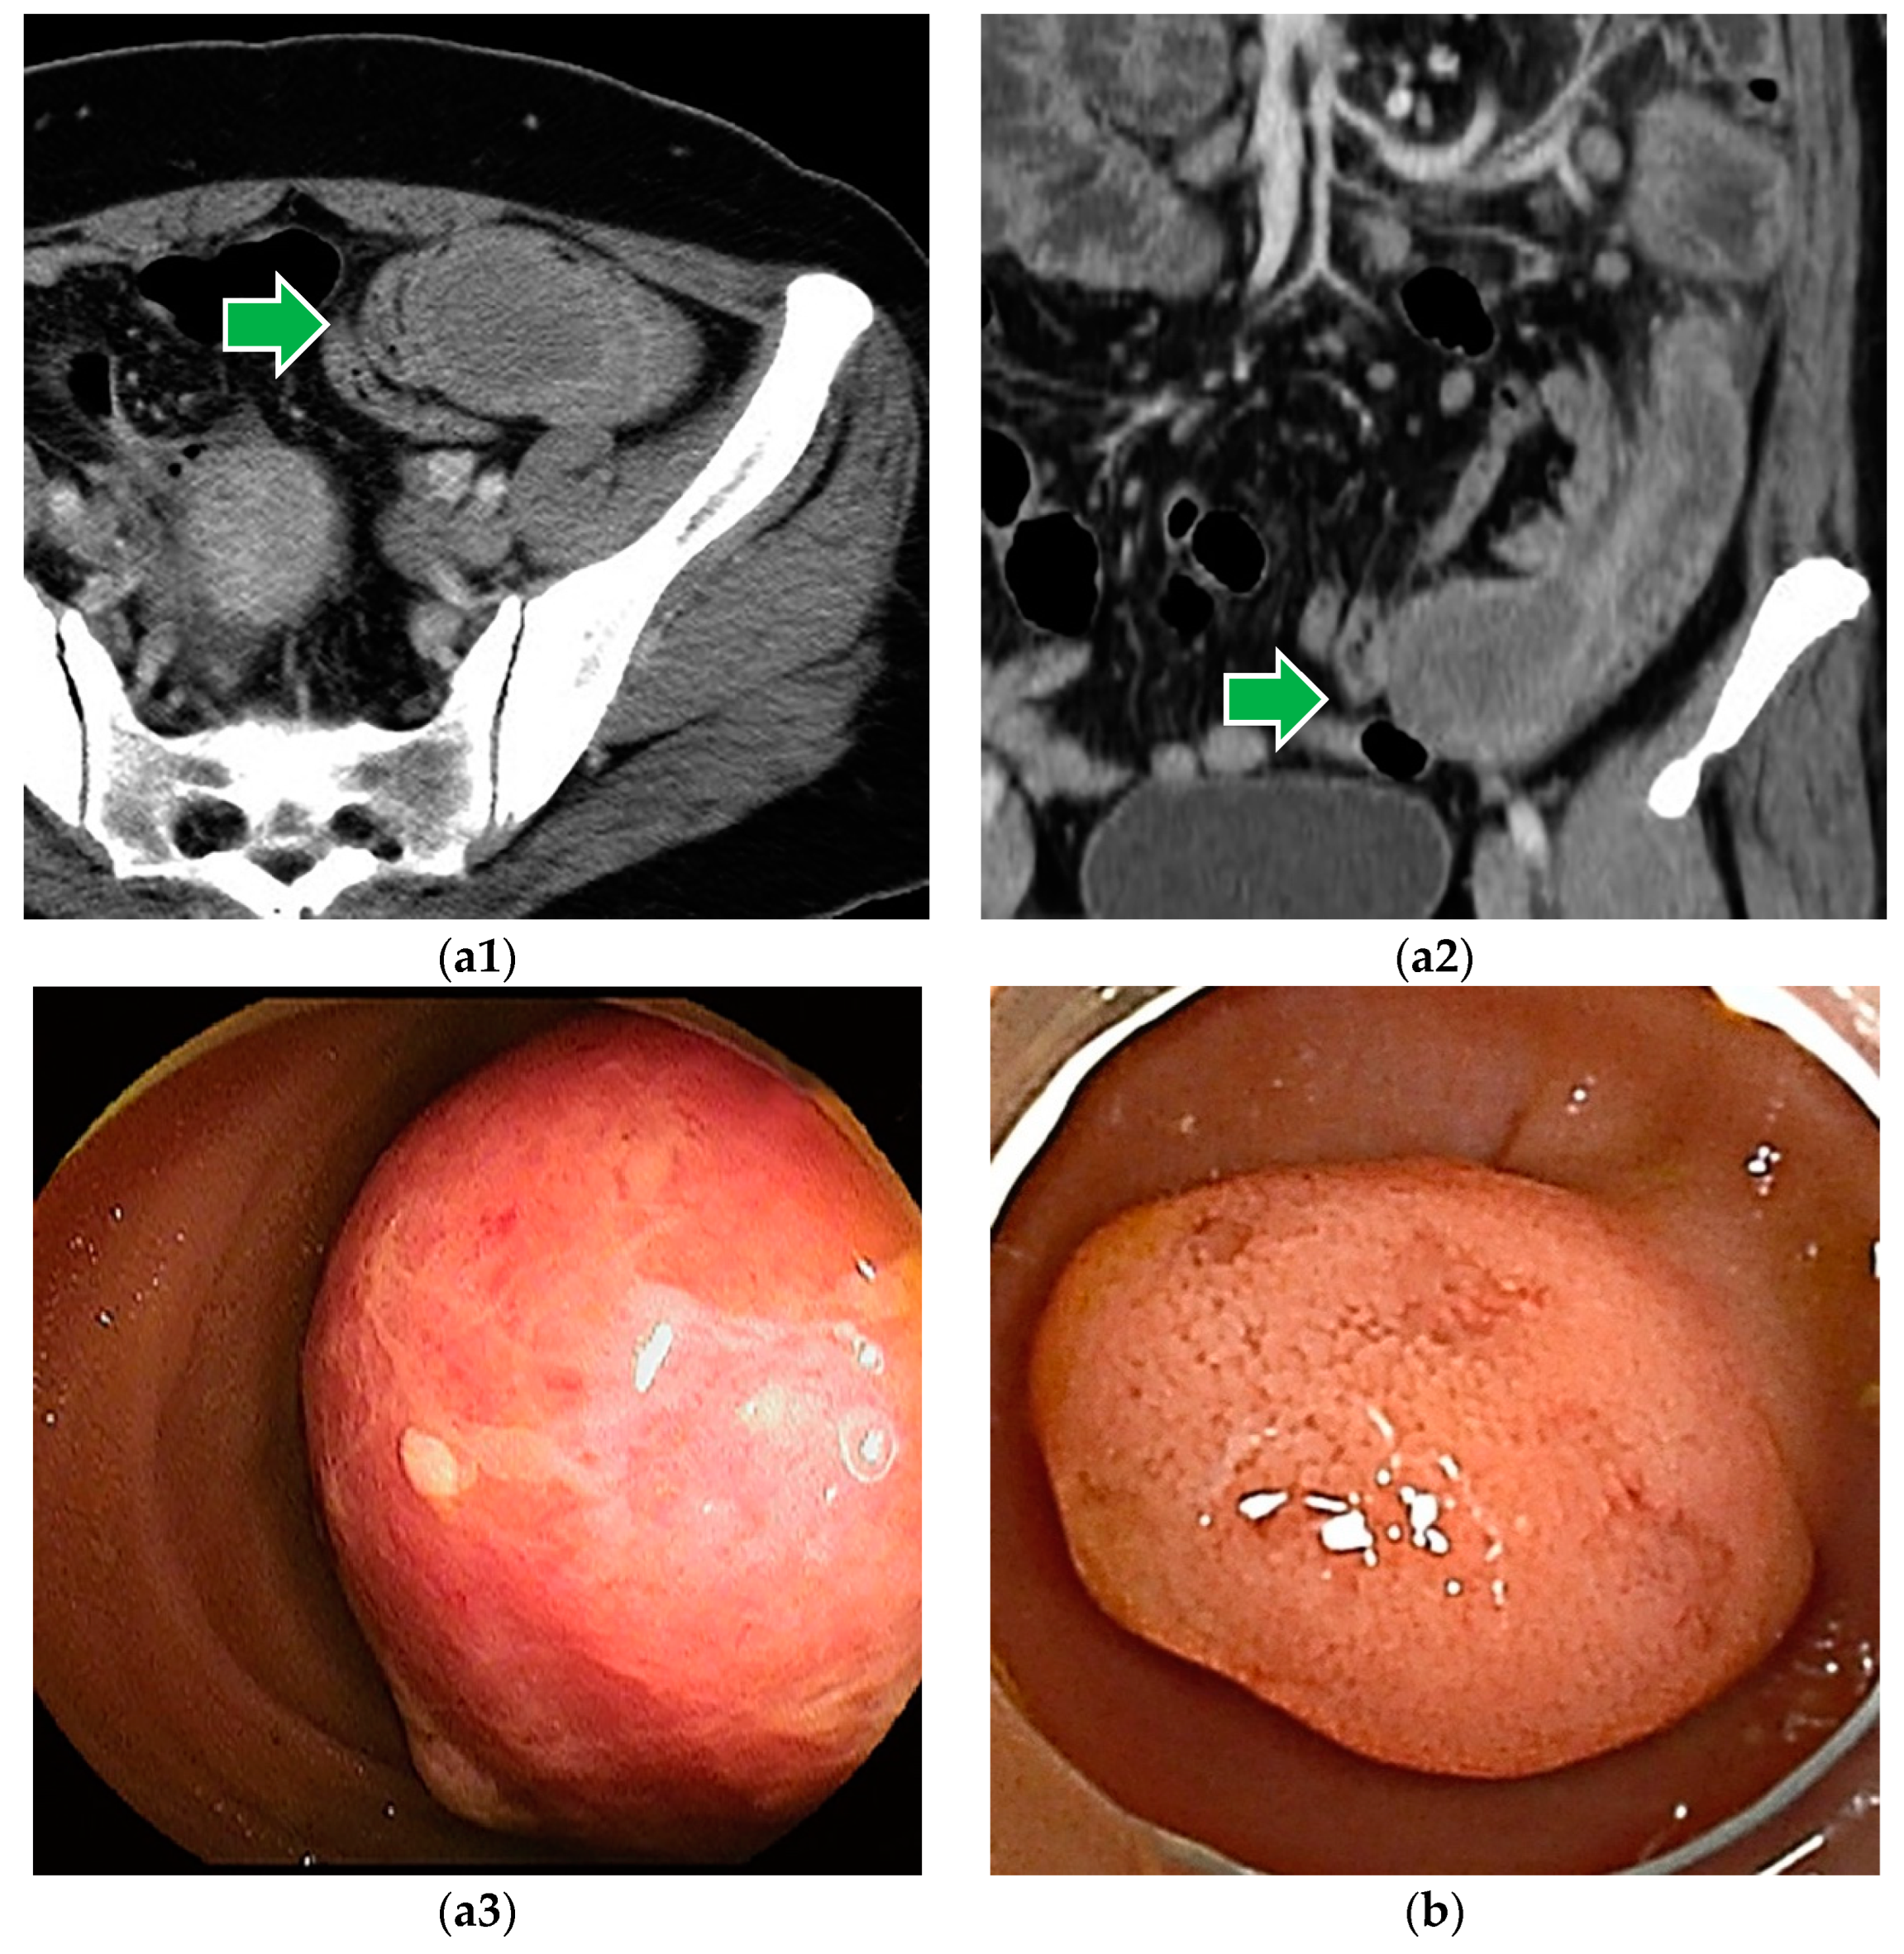

Figure 5.

Metastatic tumors: (a) metastatic jejunal tumor from angiosarcoma of the breast. (b) Metastatic jejunal tumor from lung cancer.

The endoscopic image of the metastatic lesion is variable (Figure 5). Metastatic lesions can present as single or multiple polypoid lesions, with or without ulcers. Metastatic tumors arise from the submucosa and are sometimes difficult to distinguish from malignant lymphomas on endoscopic images. They may be seen as focal bowel wall thickening and cause luminal narrowing.